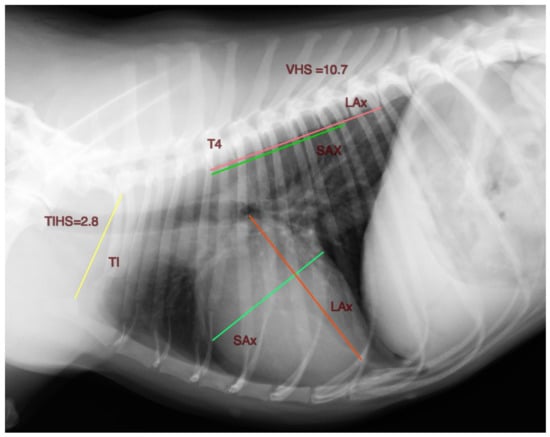

Based on the VHS, a method to measure the cardiac silhouette indexed to the thoracic inlet is presented. The length of the long and short axes of the cardiac silhouette, measured as described previously for the VHS, were summed and divided by the corresponding thoracic inlet length (TI). The TI is the distance extending from the cranio-ventral aspect of the first thoracic vertebra to the craniodorsal manubrium at its highest point, the point of the minimum length of the thoracic inlet. A unitless value, the Thoracic Inlet Heart Score (TIHS), is obtained (Figure 1).

Figure 1.

Right lateral thoracic radiographic projection of a clinically normal 9 years old chihuahua illustrating the thoracic inlet heart size measurement method (THIS). The long axis (LAx) and short axis (SAx) of the heart and the thoracic inlet (TI) are measured. The sum of the LAx and SAX is divided by the TI to obtain the thoracic inlet heart size. VHS Vertebral Heart Size.